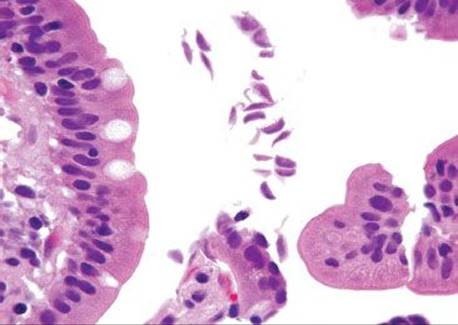

Figure 3.318 Isosporiasis. On higher power, the Isospora organisms (arrowheads) are seen embedded within the epithelium. Unless the epithelial compartment is diligently inspected in every biopsy, these organisms would almost certainly be missed.

Isosporiasis is among the more common protozoan causes of severe diarrhea in AIDS patients (Figs. 3.316–3.318).190 The Isospora belli organisms are spread via contaminated water or fecal–oral contamination. They localize to the small bowel surface and are exceedingly easy to miss owing to sometimes unremarkable background mucosa and sparsely distributed organisms (Figs. 3.316–3.321). Diagnostic confirmation is facilitated through identification of the oocysts in stool samples or duodenal aspirates.191 Standard therapy consists of trimethoprim–sulfamethoxazole, which is often long term in severely immunocompromised patients.